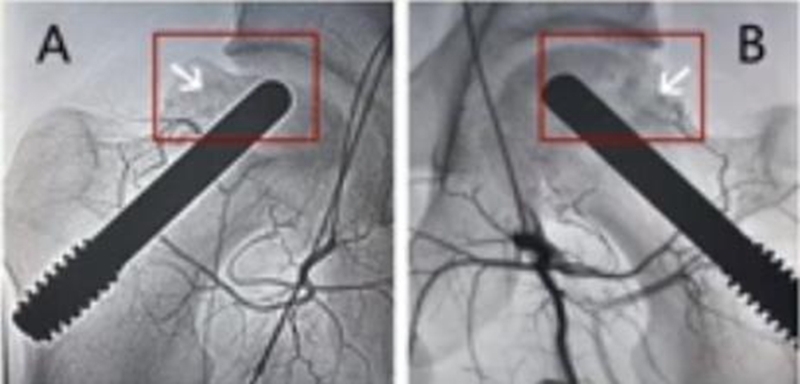

因髓芯减压联合非血管化骨移植术仍有待进一步研究,有学者就提出了髓芯减压联合血管化骨移植。血管化的移植骨块主要源于腓骨或者髂嵴,由于保留了血管,因此有助于改善坏死区的血运,促进坏死区域骨组织的修复重建。

Urbaniak等人报告了103例,血管化胖骨移植治疗股骨头坏死,Ⅱ期患者五年存活率为91%,Ⅲ期患者五年存活率为77%。Eward和Yoo等人的研究,血管化腓骨移植治疗股骨头坏死,Ⅱ期存活率为89%(平均随访13.9年)和Ⅲ期存活率为75%(平均随访14.4年)。Plakseychuk等人的进一步研究,回顾性地比较了血管化胖骨移植术与非血管化腓骨移植术,发现血管化腓骨移植队列的临床结局有更好的改善。笔者认为,血管化的骨移植将是今后发展的一个方向。